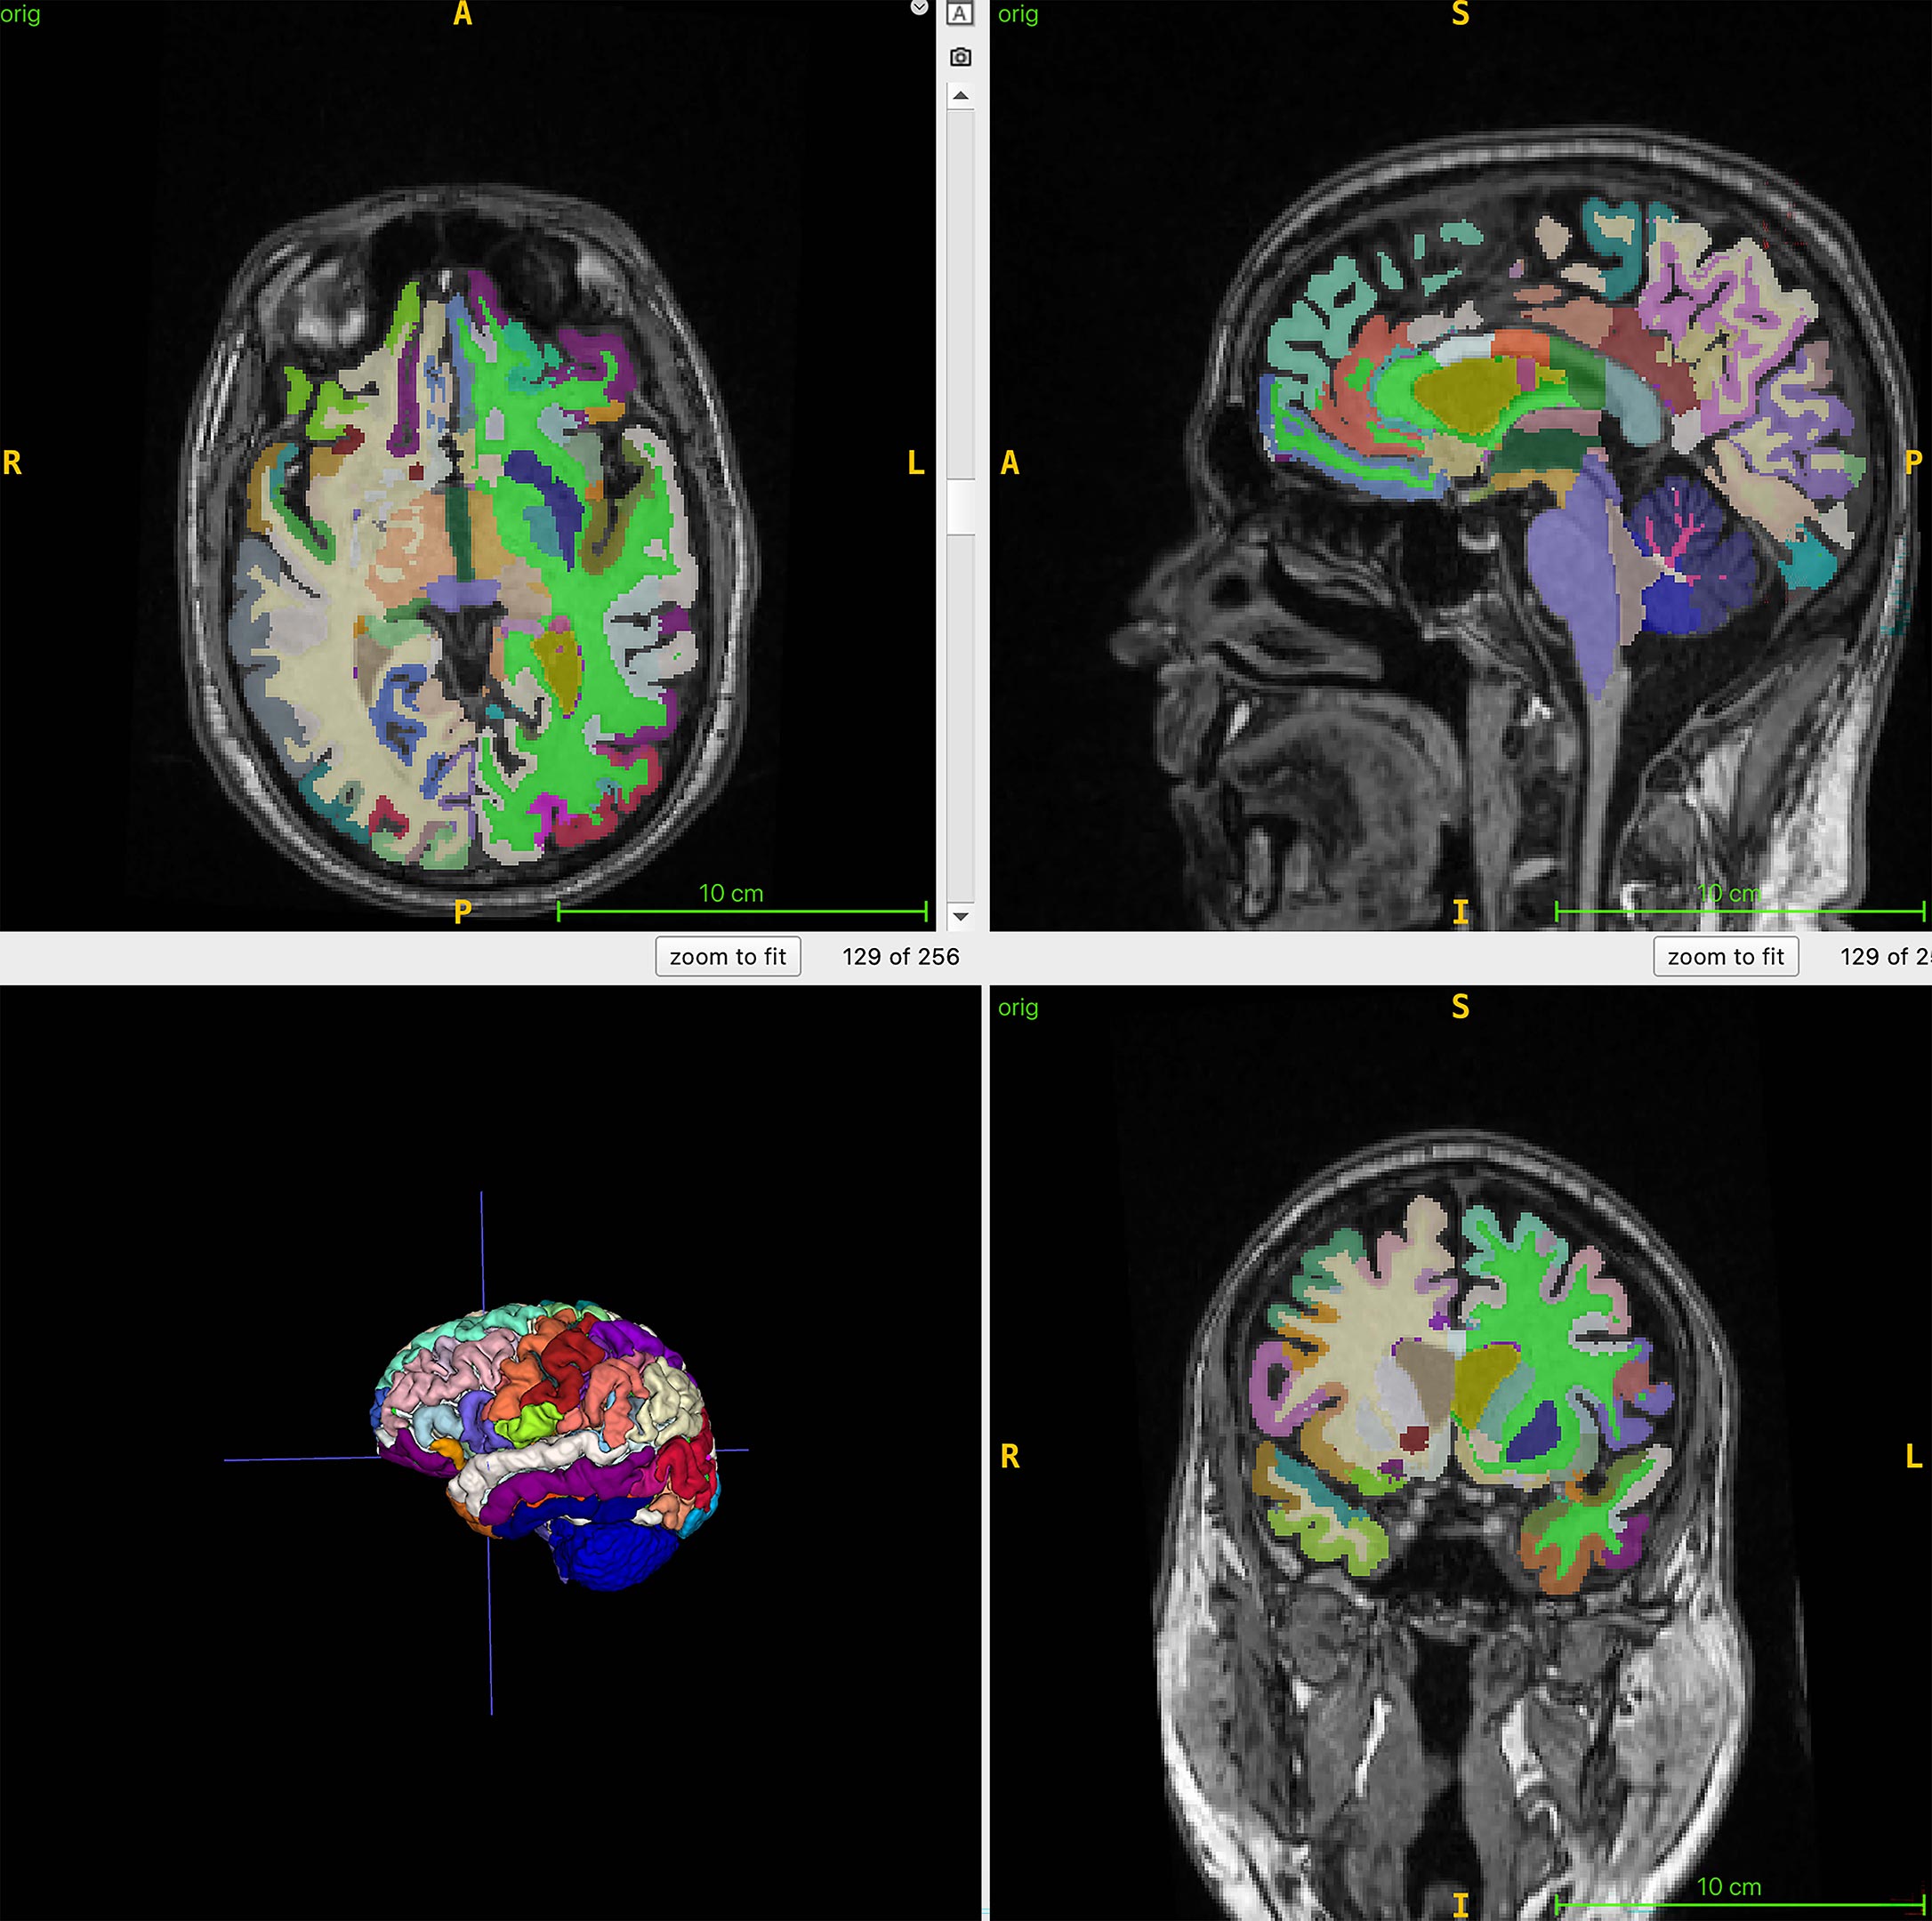

Во время исследования, которое сейчас еще продолжается, ученые обследовали с помощью МРТ тела 1164 здоровых человек из четырех клиник. Женщин среди них было 52%. Средний возраст участников — 55,17 года. Ученые использовали Т1-взвешенные последовательности. При использовании этого метода, жир на МРТ-снимках выглядит светлым, а жидкость — темной. Это помогает оптимально визуализировать мышечную, жировую и мозговую ткани. Алгоритм искусственного интеллекта авторы использовали, чтобы количественно оценить общий нормализованный объем мышц, висцерального жира на животе, подкожного жира и возраста мозга.